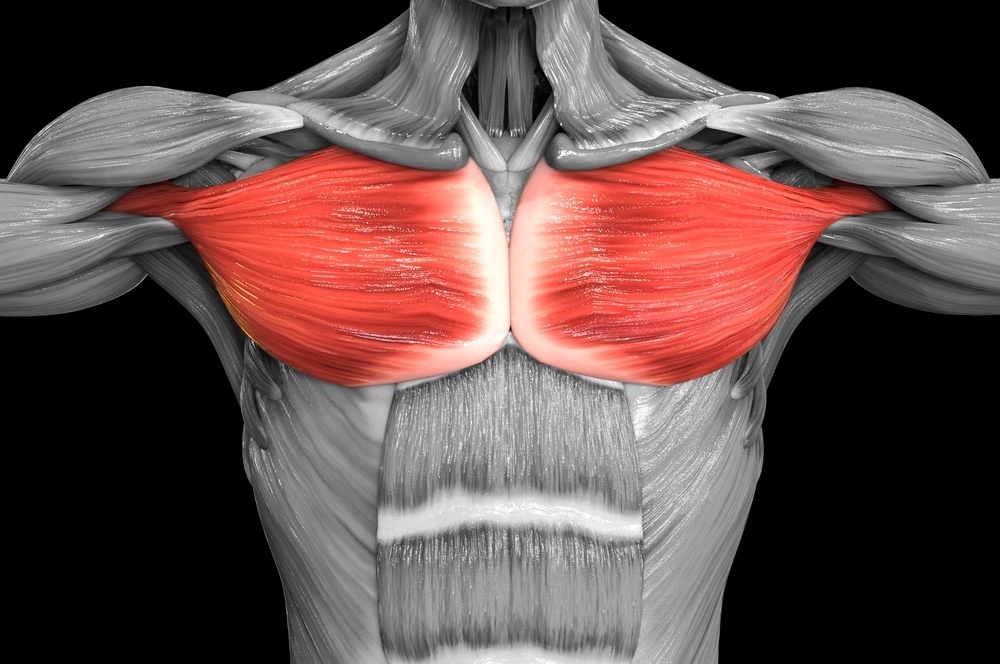

Quando portiamo il braccio e la mano il più possibile verso il gomito e il braccio opposti, la spalla si sposta leggermente in avanti e, soprattutto, verso la linea di mezzo del nostro corpo. Quando si trova in questa situazione, la spalla si dice addotta. Un ruolo determinante in questo movimento lo ha il muscolo pettorale. Se quest’ultimo è in stato di spasticità, la spalla rimane addotta.

L’adduzione della spalla causata dalla spasticità del muscolo pettorale forza l’articolazione producendo dolore, a volte intenso e persistente. Questa condizione non è rara dopo un ictus, ma può presentarsi anche nei bimbi, in esito di paralisi cerebrale.

Ottenere il rilasciamento di questo muscolo è particolarmente difficile, e la persistenza della spasticità tiene vivo il dolore, aprendo la strada a problematiche posturali importanti nei bambini, ostacolandone fortemente la riabilitazione.